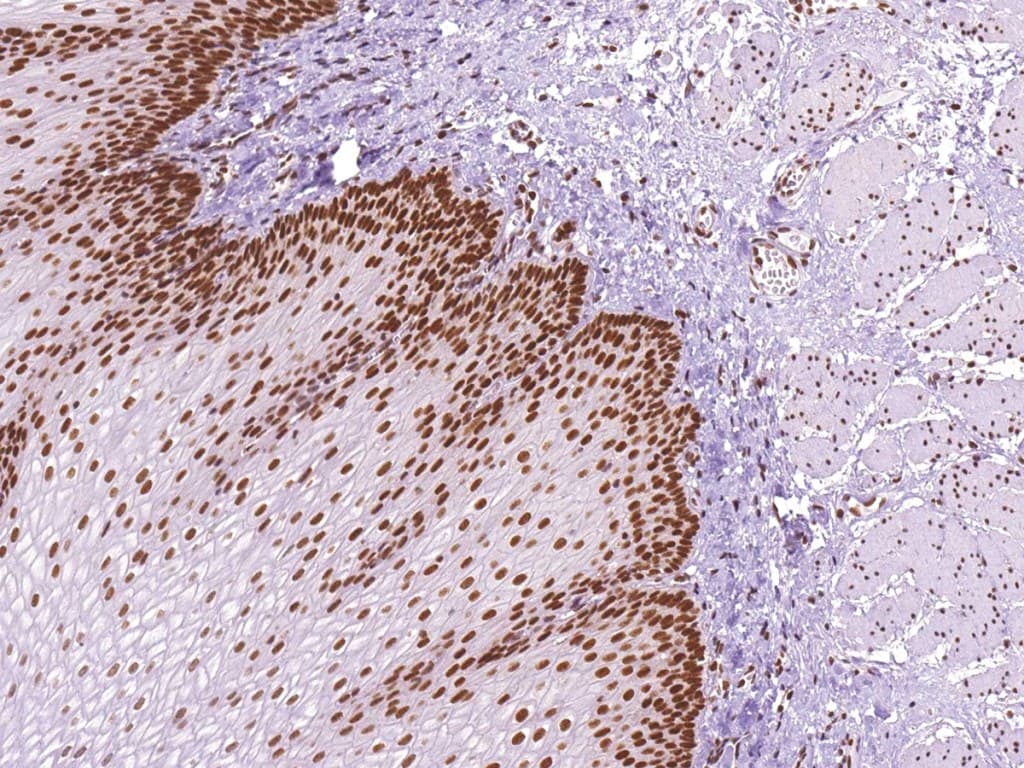

La evaluación inmunohistoquímica (IHC) de MLH1 es una herramienta diagnóstica estándar para tumores gastrointestinales. La pérdida de la tinción nuclear de MLH1 se correlaciona con un alto nivel de inestabilidad de microsatélites (MSI-H) e identifica tumores con deficiencia en la reparación de errores de apareamiento (dMMR). La IHC de MLH1 ayuda a estratificar tumores, predecir el pronóstico y guiar las pruebas moleculares, incluyendo el análisis de metilación del promotor de MLH1 o la secuenciación de línea germinal cuando se sospecha síndrome de Lynch. Su alta concordancia con las pruebas de MSI garantiza una identificación fiable del estado de MMR en cánceres colorrectales y gástricos.

- Se une específicamente a la proteína nuclear MLH1, permitiendo una detección precisa tanto en tejido tumoral como normal.

- La pérdida de tinción nuclear de MLH1 indica deficiencia de MMR; una tinción intacta refleja un sistema MMR competente (pMMR).